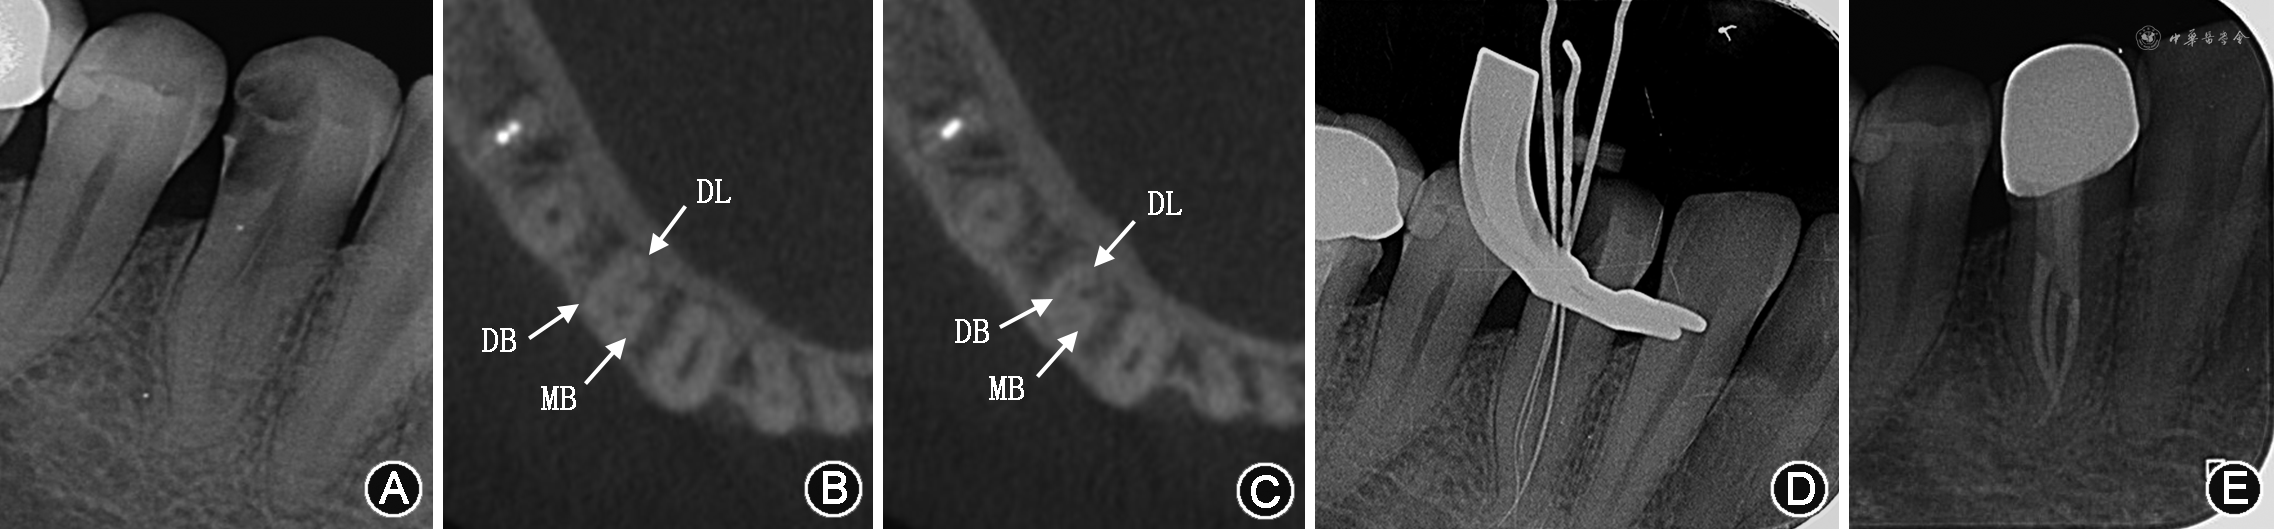

3.牛牙症和C形根管:牛牙症是一种髓腔内部形态变异,最早于1913年由Keith教授在描述史前人类尼安德特人牙齿化石时提出。牛牙症的牙齿在釉质牙骨质界处缺乏收缩,其特征是髓室垂直向延长、髓室底顶端向根方移位以及牙根分叉[29]。这种倾向与偶蹄目动物,特别是公牛的牙齿情况类似,因而命名为牛牙症[30]。Madeira等[31]研究认为,牛牙症的诊断应包括以下几点:①牙颈部无明显缩窄;②宽的棱柱形牙根,从牙颈部到根尖部牙根的直径大致相同;③根尖部膨大、分叉、顶端略凹;④髓腔宽大并于根尖处分叉。基于上述标准,Madeira等[31]认为下颌第一前磨牙这种根管宽大分叉的特点并不足以作为诊断牛牙症的指征,更倾向于这是下颌第一前磨牙根管变异的一种常态,其研究报道下颌第一前磨牙牛牙症的发生率为0.42%。值得注意的是,一些双根的下颌第一前磨牙,其粗大的管腔通常在釉质牙骨质界下6~7 mm甚至更低的位置分叉[32]。本课题组收治的1例左下颌第一前磨牙根管治疗患者,呈现典型的如Madeira等[31]描述的特征(图2),其牙冠牙颈部无明显缩窄,根管上段管腔粗大,于根尖1/3分成3个独立根管,属于典型的牛牙症患牙。此外,Aricioğlu等[33]研究显示,牛牙症与C形根管的发生高度相关,国内亦有相关病例报道[7],临床医师在治疗牛牙症患牙时需警惕患牙可能同时存在C形根管系统(图3)。

C形根管是存在于牙根横截面形态呈C形的牙根中的根管系统。C形根管在Vertucci分类中被归为“其他类型”,因其根管系统复杂,在下颌第一前磨牙研究中常被单独分类研究,有报道显示C形根管在不同种族中的发生率存在差异[12]。体外研究发现我国人群C形根管发生率高达24%[34];体内研究显示我国人群C形根管的发生率为0.5%~12.2%[22,35]。研究结果的差异可能与研究的样本量和评价方法不同有关。C形根管的结构可发生于根管的任何位置,Gu等[36]研究显示下颌第一前磨牙C形根管常发生于釉质牙骨质界下方6~11 mm,Ordinola-Zapata等[37]研究亦表明C形根管好发于根中和根尖1/3。在C形根管好发的下颌第二磨牙,临床上常可通过直视观察髓室底的形态呈C形进行识别,而下颌第一前磨牙C形根管因其冠部髓腔狭小,髓室底位置深,几乎不能通过直视识别,同时因操作空间有限,根管开口相对隐蔽,给根管的定位、清理、成形和充填带来挑战。

分辨率高的显微CT常用于研究离体牙的根管结构,目前还不能用于临床。有研究表明,锥形束CT和显微CT在鉴别根管形态上具有高度的一致性[42]。近年锥形束CT因其分辨率高,能快速提供牙体及周围硬组织的三维影像结构,已被广泛应用于根管形态的临床诊断和研究。小视野高分辨率的锥形束CT能更精确地展示复杂根管的解剖细节[43],使临床医师能直观看到被治疗牙齿的变异情况,评估治疗难度,制订合理的治疗方案。锥形束CT的不足之处在于当根管内有充填物时,其产生的伪影可影响医师对根管实际情况的判断。因此,需结合临床和多个影像结果进行最终的评估诊断。